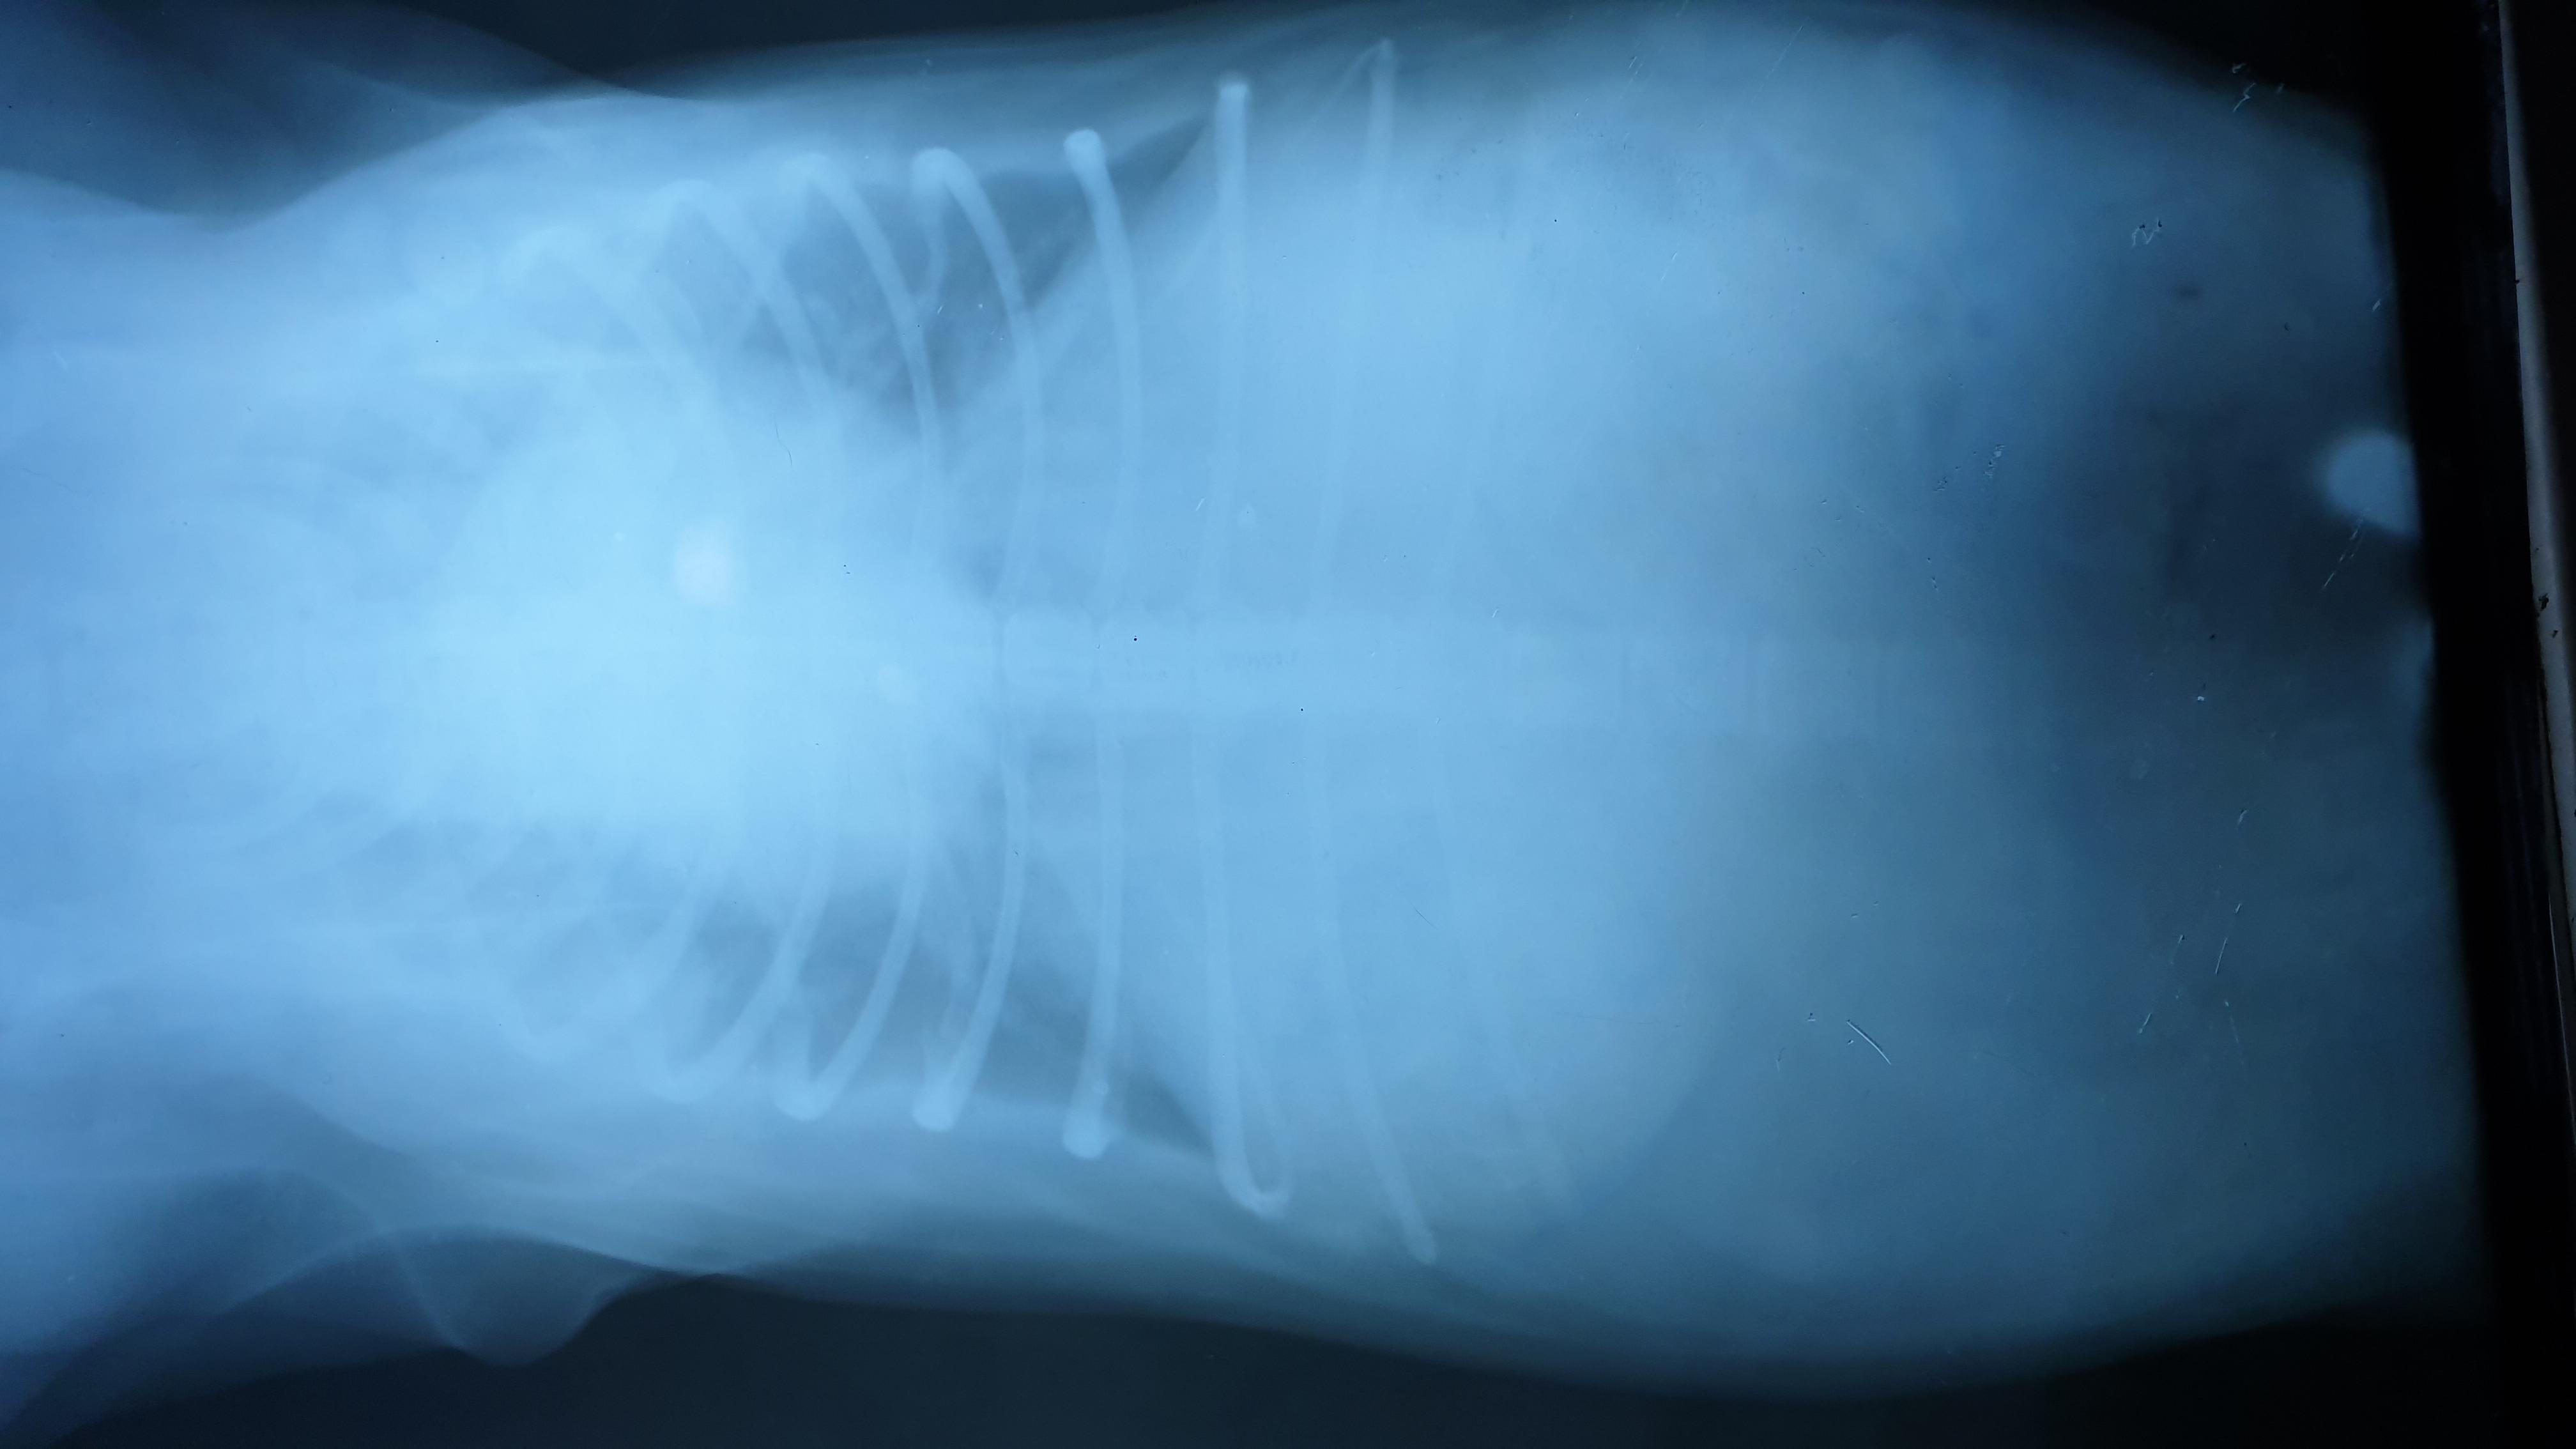

Hi! My pet was recently diagnosed with Enlarged Heart and the vet we consulted prescribed Furosemide (40mg) and Enalapril (5mg) 2x a day. The vet also prescribed Royal Canin "Satiety" for weight loss and low sodium. I am wondering if I can give my dog a natural diet in conjunction with the medication and a little of the kibble. I have been doing a lot of research and want to blend kale, spinach and brocolli and othervegetables to give to my pet. do you recommend Fish Oil too? Let me know thanks.

While these vegetables are okay to add in as a supplement I would make sure that kibble is 90% of the diet to avoid nutritional deficiencies. Recently there has been some concern about boutique, grain free and exotic ingredient diets and a link to dilated cardiomyopathy which could cause heart enlargement, and it seems like kibble from larger companies like Royal Canin are the safest option. Fish oil may be beneficial for dogs with cardiac disease.